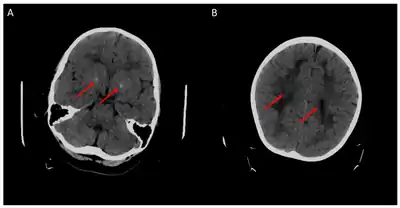

Cerebral CT-scan at 4 years old. Red arrows show brain calcifications (A) and diffuse white matter abnormalities (B). From Mafi et al., 2020[10]

Children with the FOLR1 mutation are born healthy. Symptoms typically appear at about 5 to 24 months of age. The symptoms get worse with time. Without treatment there may be poor muscle tone, trouble with coordination, trouble talking, and seizures.[2][3] In addition, signs of psychomotor retardation, sleep disturbances, cerebellar ataxia, and delayed development of head growth can occur. At around age three, visual disturbances can develop, and sensorineural hearing loss can occur at around age six.[11] In children with cerebral folate deficiency, the cerebrospinal fluid shows low levels of 5MTHF, and a loss of white matter in the brain (leukodystrophy) may occur. As a result of the decreased levels of 5MTHF, the child experiences low levels of Vitamin B folate.[12]  There is inability for the 5MTHF to be transported across the blood-brain barrier, resulting in symptoms of seizures, delayed cognitive and motor processing, and autistic features.[13]